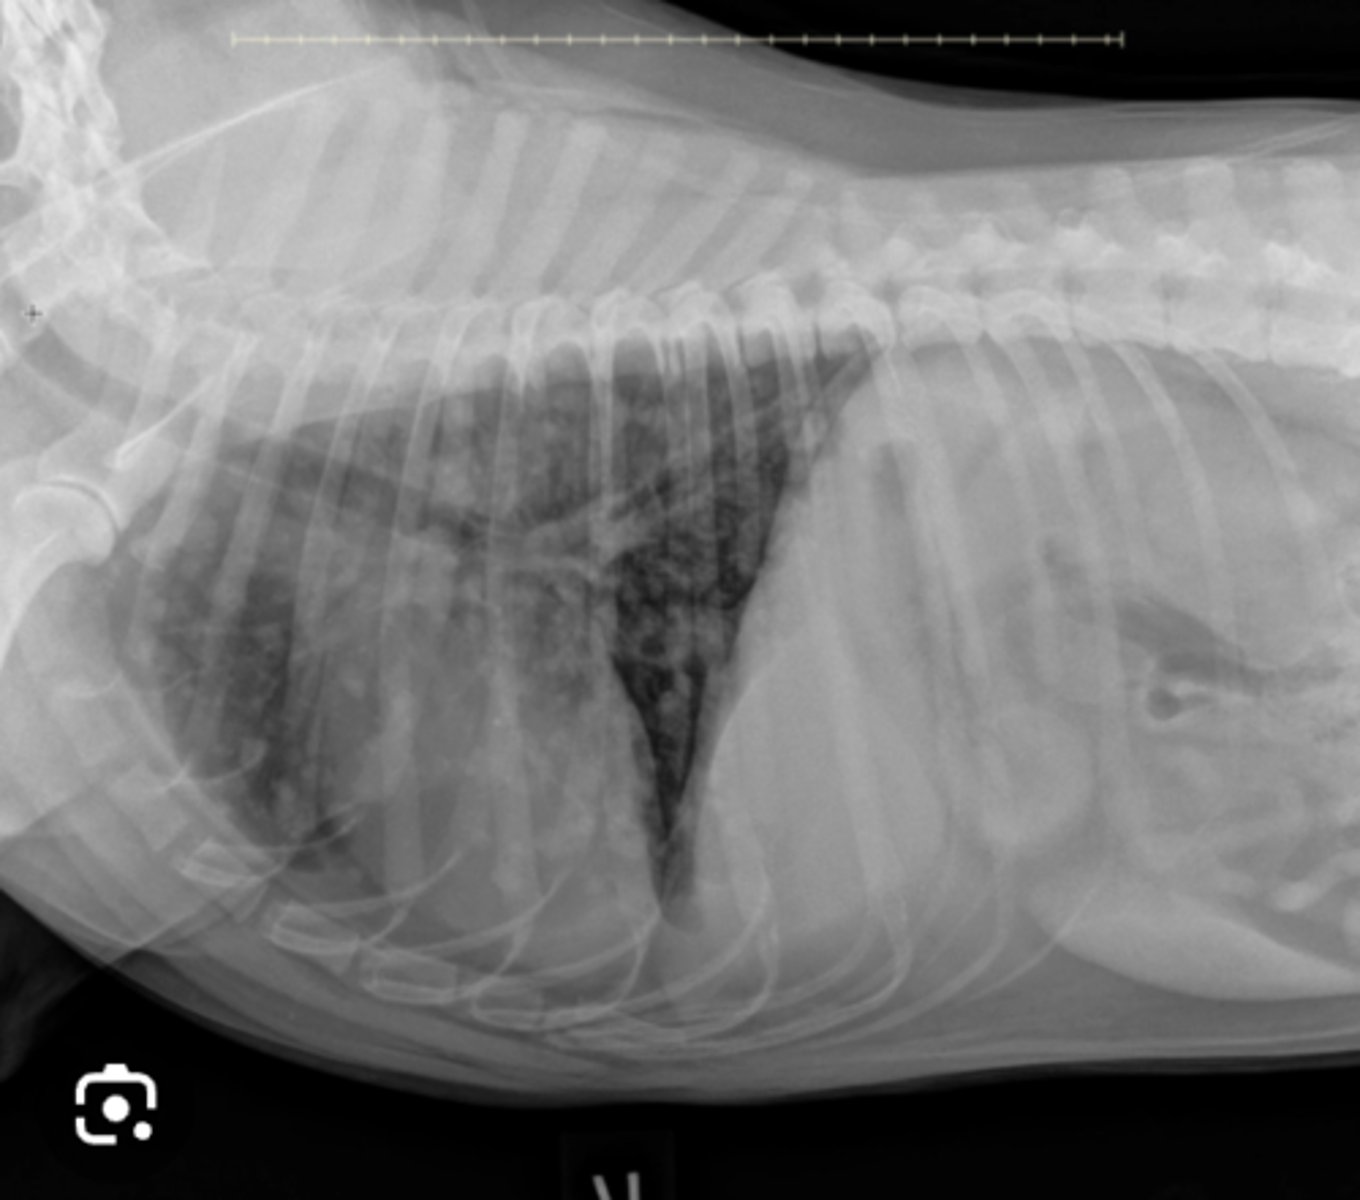

Cardiomegaly from left atrial enlargement

Image of 6yo terrier with cardiac murmur and raspy lung- what do you see?